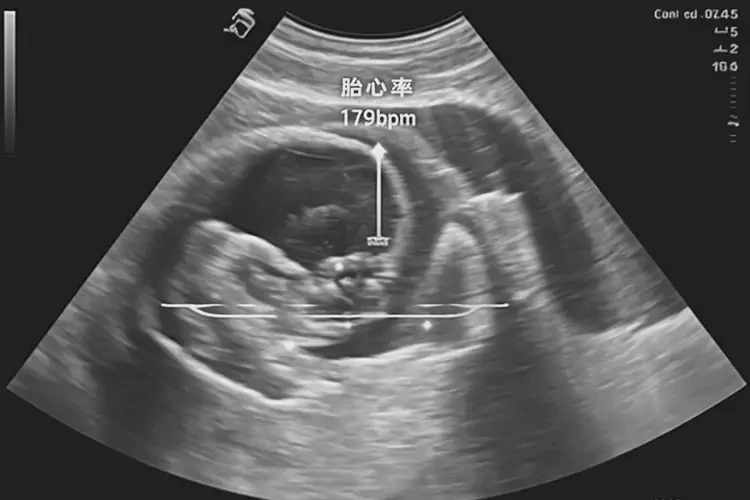

孕9周5天胎心179還能保住嗎

胎心率179次/分鐘在孕9周5天屬于正常范圍,胎兒通常可以保住。

孕9周5天時,胎兒的胎心率在120-180次/分鐘之間都被認為是正常的。胎心率179次/分鐘雖然接近上限,但并不意味著胎兒有危險。以下是詳細的分析和建議:

孕9周5天胎心179還能保住嗎(圖1)